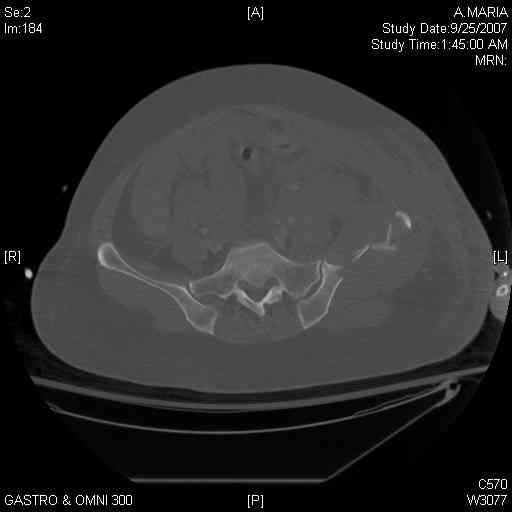

It's a comminuted iliac fracture involving the GS notch and all that

implies...use the lateral interval of an ilioinguinal, sequentially reduce,

and fix...if you want to, you can attach the dominant unstable fragment to

both the stable posterior iliac fragment and also to the anterolateral portion of the sacrum using plates...if you choose to anchor to both, the implants get congested on the iliac side of the SI joint so be precise with contouring and such applications...perhaps and based on the images shown, an iliosacral screw would only augment the construct if applied to the second sacral segment (but this is difficult to assess on the images shown). The crest components can be held securely with screws and/or peripheral plating.

Thanks. I probably didn't include enough images on the CT, but it didn't look to me like an SI screw would be of value except into S2, which I am not

comfortable placing. I will post finals if the neurosurgeons let me operate on her. ICPs still a problem.